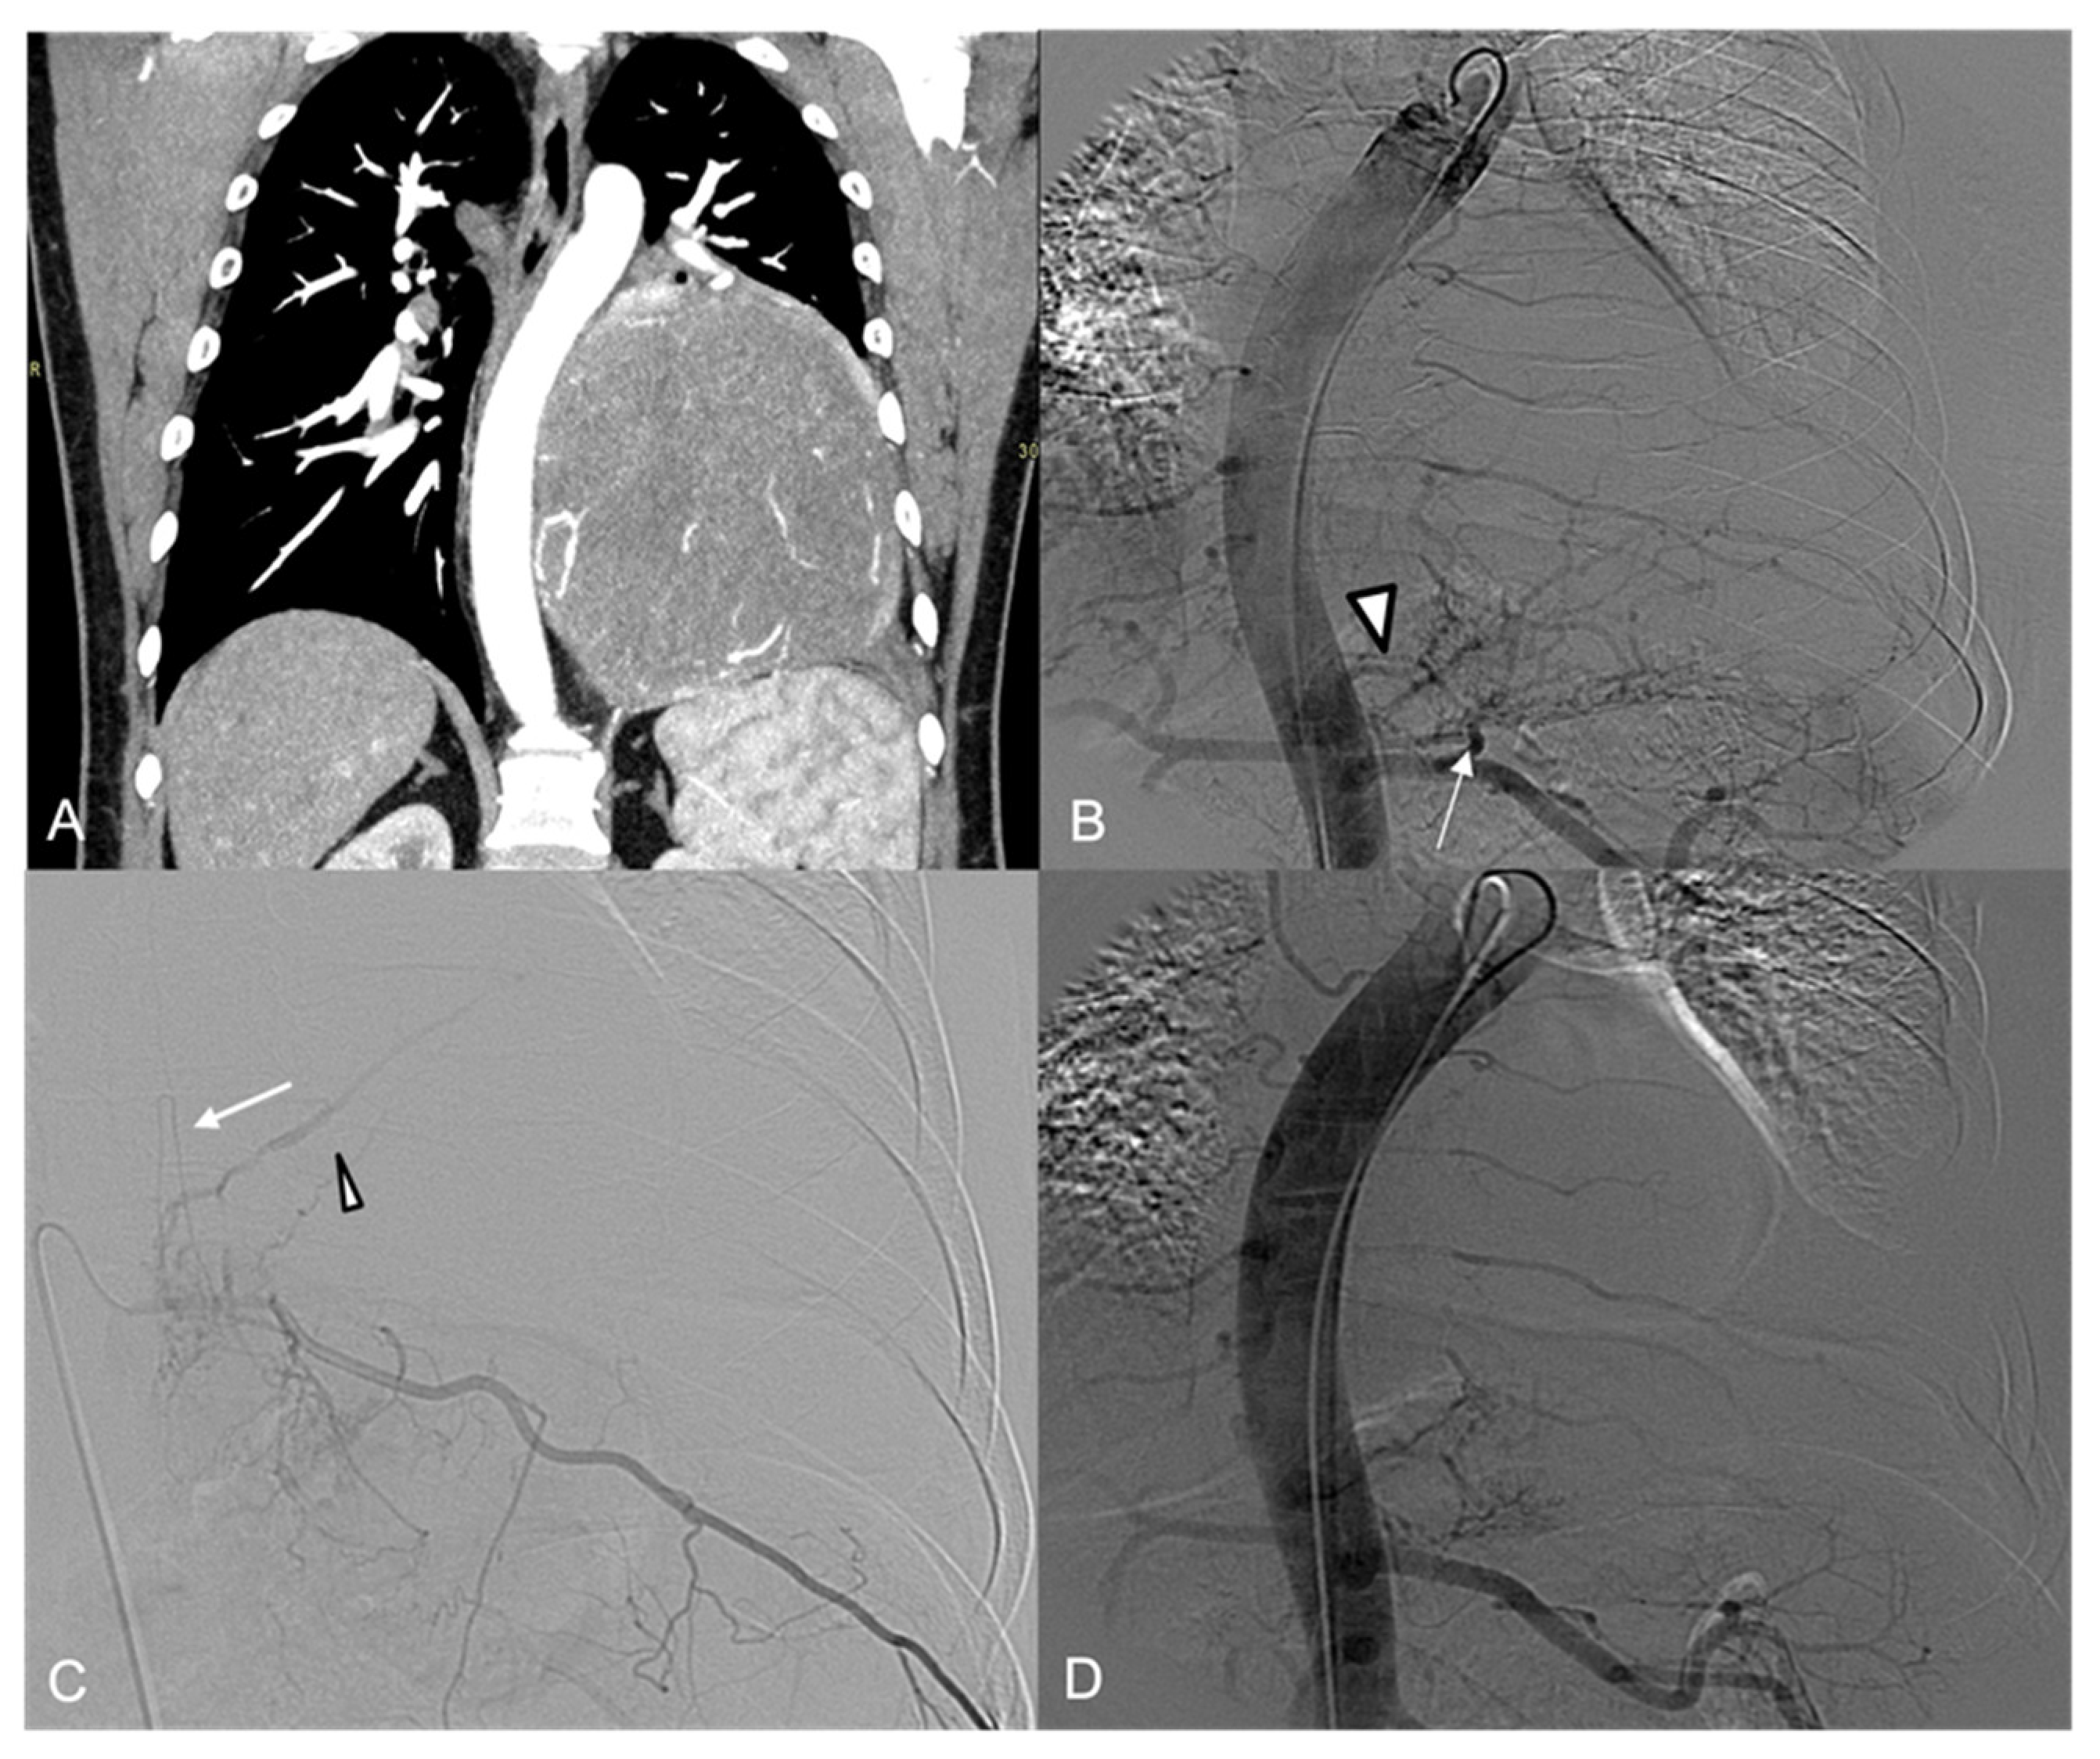

3. Results